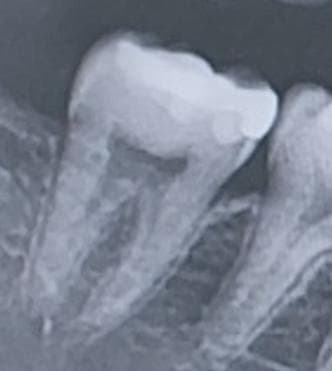

사진 47번에 위치한 어금니쪽 인레이를 한 부위가 옛날 중학교 시절 쯤 했던 인레이입니다. (현재 25살) 그렇다보니 시간이 경과해서 틈이 생겨 충치가 진행된 것처럼 보이는데 현재 증상으로는 해당 부위에 차가운물이 닿게 되었을 시 정말 미미하게 시린 경험을 겪고 있습니다. 하지만 지금 의문이 드는 점이 제가 치간칫솔을 최근에서 들어가는 공간이 되었는 것을 확인하고 치간칫솔을 무리하게 사용한건지 그것 때문에 시리게 된건지도 모르겠습니다.

일단 이번주 금요일에 치과 예약이 잡혀 있어서 그때 물어보기도 할 예정이나, 육안으로 보았을때 크게 검은색이 제 눈에는 보이지 않아서 다른 선생님들의 조언을 받고자 올립니다.

만약 치료를 하게 된다면 다시 인레이를 씌우는 정도로 될 것 같은지도 알려주시면 감사하겠습니다.

• 1번 째 사진

인레이 하방 이차충치가 의심되긴하나 신경에 근접하지 않았고, 치주인대 상태도 괜찮아보입니다 신경치료가 필요하진 않을 것 같고 다시 인레이 해주면 될 것 같습니다

충치를 제거해봐야 알겟지만 충치가 깊이 진행된것처럼 보이진 않아서 다시 인레이 치료를 하셔도 될것같습니다.